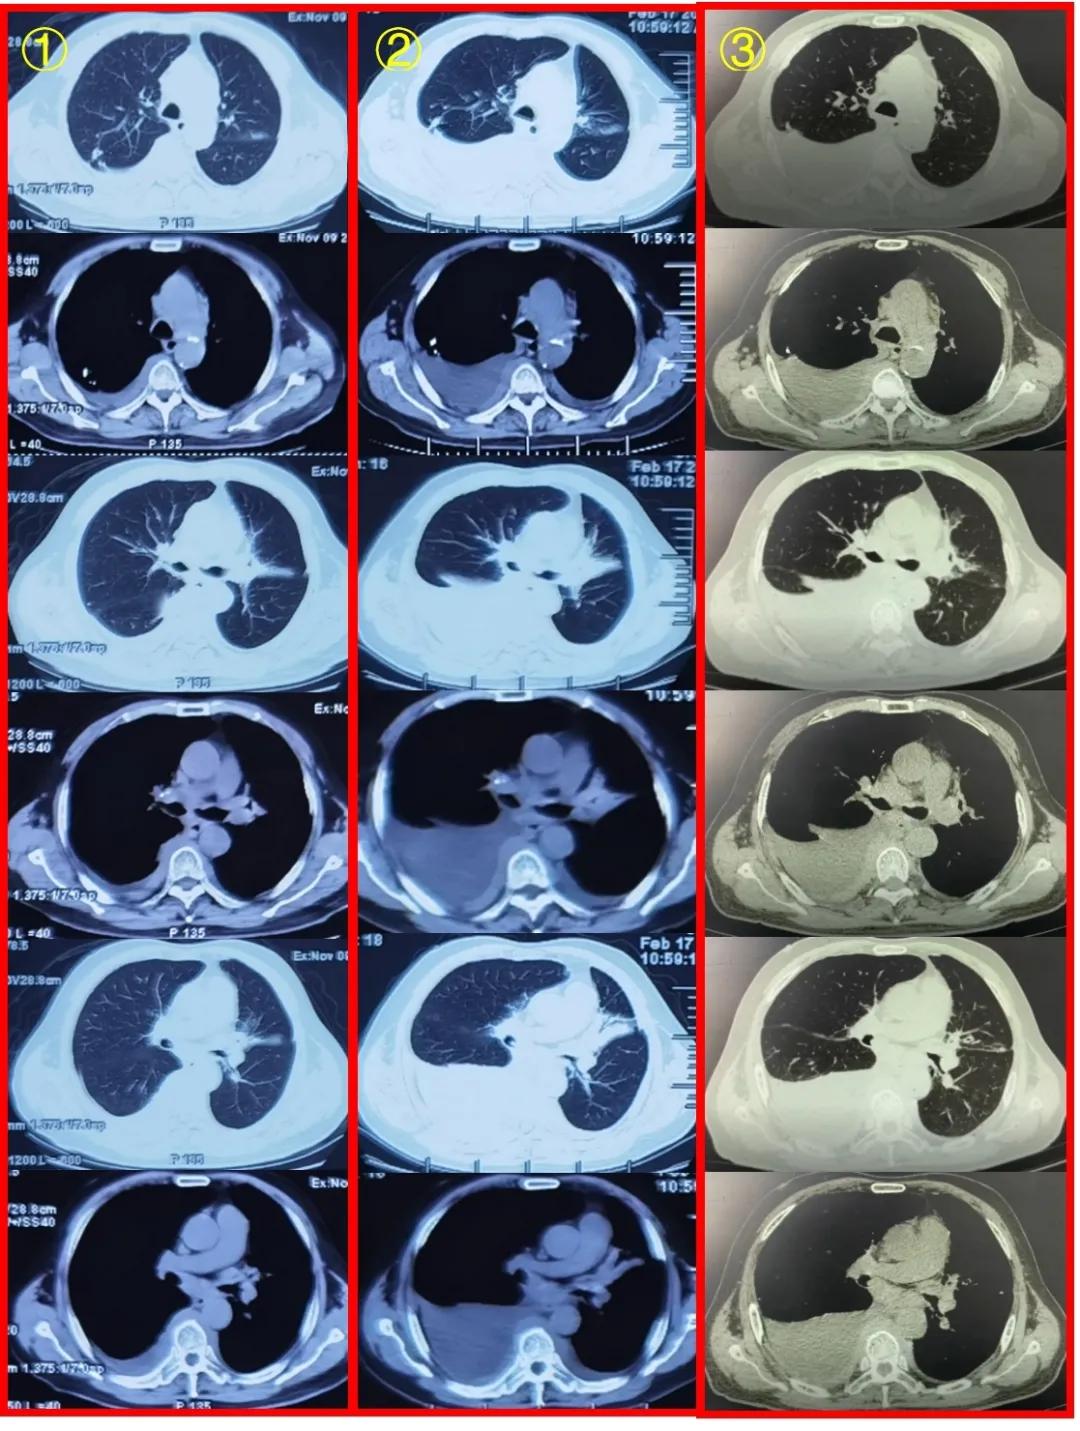

CT报告,患者原发性支气管肺癌伴纵隔,两肺门,横隔组,肝胃间隙多发淋巴结转移,双侧胸膜转移,包绕血管并右侧胸腔及叶间积液。胸部增强CT(2020年9月10日 上海市某三甲医院):左肺上叶支气管狭窄,伴周围软组织影,纵隔内肿大淋巴结伴融合,两肺胸膜增厚,两侧胸腔积液,恶性待排。主动脉弓旁条状低密度影。右肺上叶钙化灶,右肺中叶斑片状磨玻璃影。胸部CT增强(2021年5月28日 上海市某三甲医院)(图4):

图4:胸部CT平扫对比:①2020年11月9日南昌市某三甲医院(抗感染治疗后复查);②2021年2月17日南昌市某三甲医院(症状加重后复查,抗结核治疗前);③2021年5月21日上海市某三甲医院(抗结核治疗后复查)

从CT影像学我们可以看到,患者左肺上叶支气管狭窄,伴周围软组织影,纵隔肿大淋巴结伴融合,两侧胸膜增厚,右侧液气胸引流中,左侧胸腔积液;较2021年5月21日右侧胸腔积液减少、积气新发。主动脉弓旁条状低密度影,建议结合临床病史。右肺上叶钙化灶,右肺中叶斑片磨玻璃影。后纵隔软组织影:至此,引出一个思考,是纵隔纤维化吗?